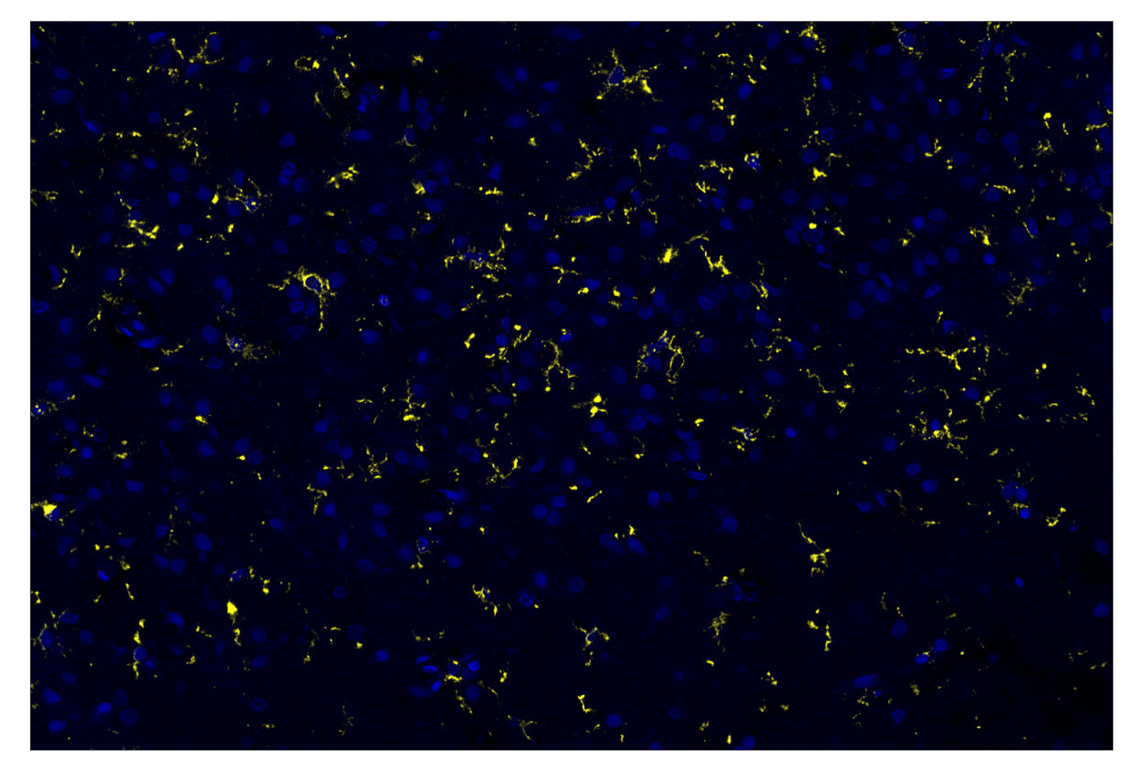

Iba1/AIF-1 (E4O4W) & CO-0100-647 SignalStar Oligo-Antibody Pair #84747

Iba1/AIF-1 (E4O4W) XP® Rabbit mAb (SignalStar™ Conjugate 0100) recognizes endogenous levels of total Iba1/AIF-1 protein.

Human, Mouse

Ionized calcium-binding adaptor molecule 1 (Iba1), also known as allograft inflammatory factor 1 (AIF-1), is an evolutionarily conserved cytoplasmic calcium binding protein containing a central pair of EF-hand calcium binding motifs (1,2). Iba1/AIF-1 was originally cloned from activated macrophages in human atherosclerotic allogenic heart grafts undergoing chronic transplant rejection as well as from rat monocytes (3,4). Its function is not very well understood, but Iba1/AIF-1 expression is upregulated in response to interferon-gamma and, therefore, could modulate macrophage-dependent immune response (3). As an F-actin-binding protein, Iba1/AIF-1 may function to remodel the actin cytoskeleton and contribute to morphological changes that correlate with various microglial/macrophage states (5). Iba1/AIF-1 is also uniquely expressed in cells of monocytic lineage and is, therefore, widely used as a marker for microglia/macrophages in the brain and other tissue (6).